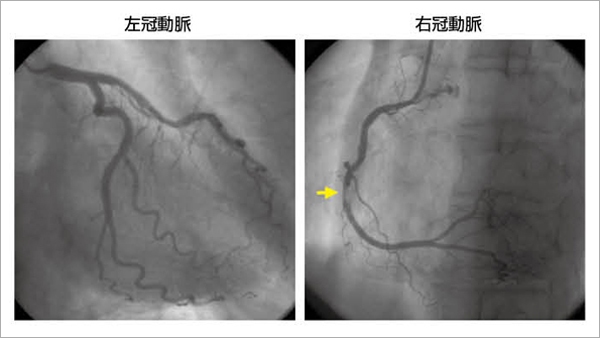

54歳,男性,2週間前からの労作性胸痛を自覚し,症状増悪するため来院。2D speckle tracking imageで下壁領域にpostischemic diastolic stunnigを認め,下壁基部から心尖部領域のtransversal strain曲線での解析では,同領域にPSSが観察されている(図5)。冠動脈造影では,右冠動脈に不安定プラークを認める(図6)。血行再建術後の2D speckle tracking imageでは,下壁領域のdiastolic stunningは消失し,transversal strain曲線も正常化しているのがわかる(図7)。

図6 図5の症例の冠動脈造影

冠動脈造影では,右冠動脈(seg 3)にプラーク破裂を認める。